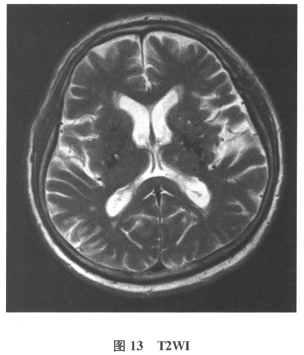

[单选题]患者男,61岁。因“发作性头晕2年,加重伴记忆力下降、走路不稳3月余”就诊。查体:BP140/70mmHg;意识清楚,构音障碍,近期记忆力及远期记忆力

[多选题]患者男,61岁。因“发作性头晕2年,加重伴记忆力下降、走路不稳3月余”就诊。查体:BP140/70mmHg;意识清楚,构音障碍,近期记忆力及远期记忆力